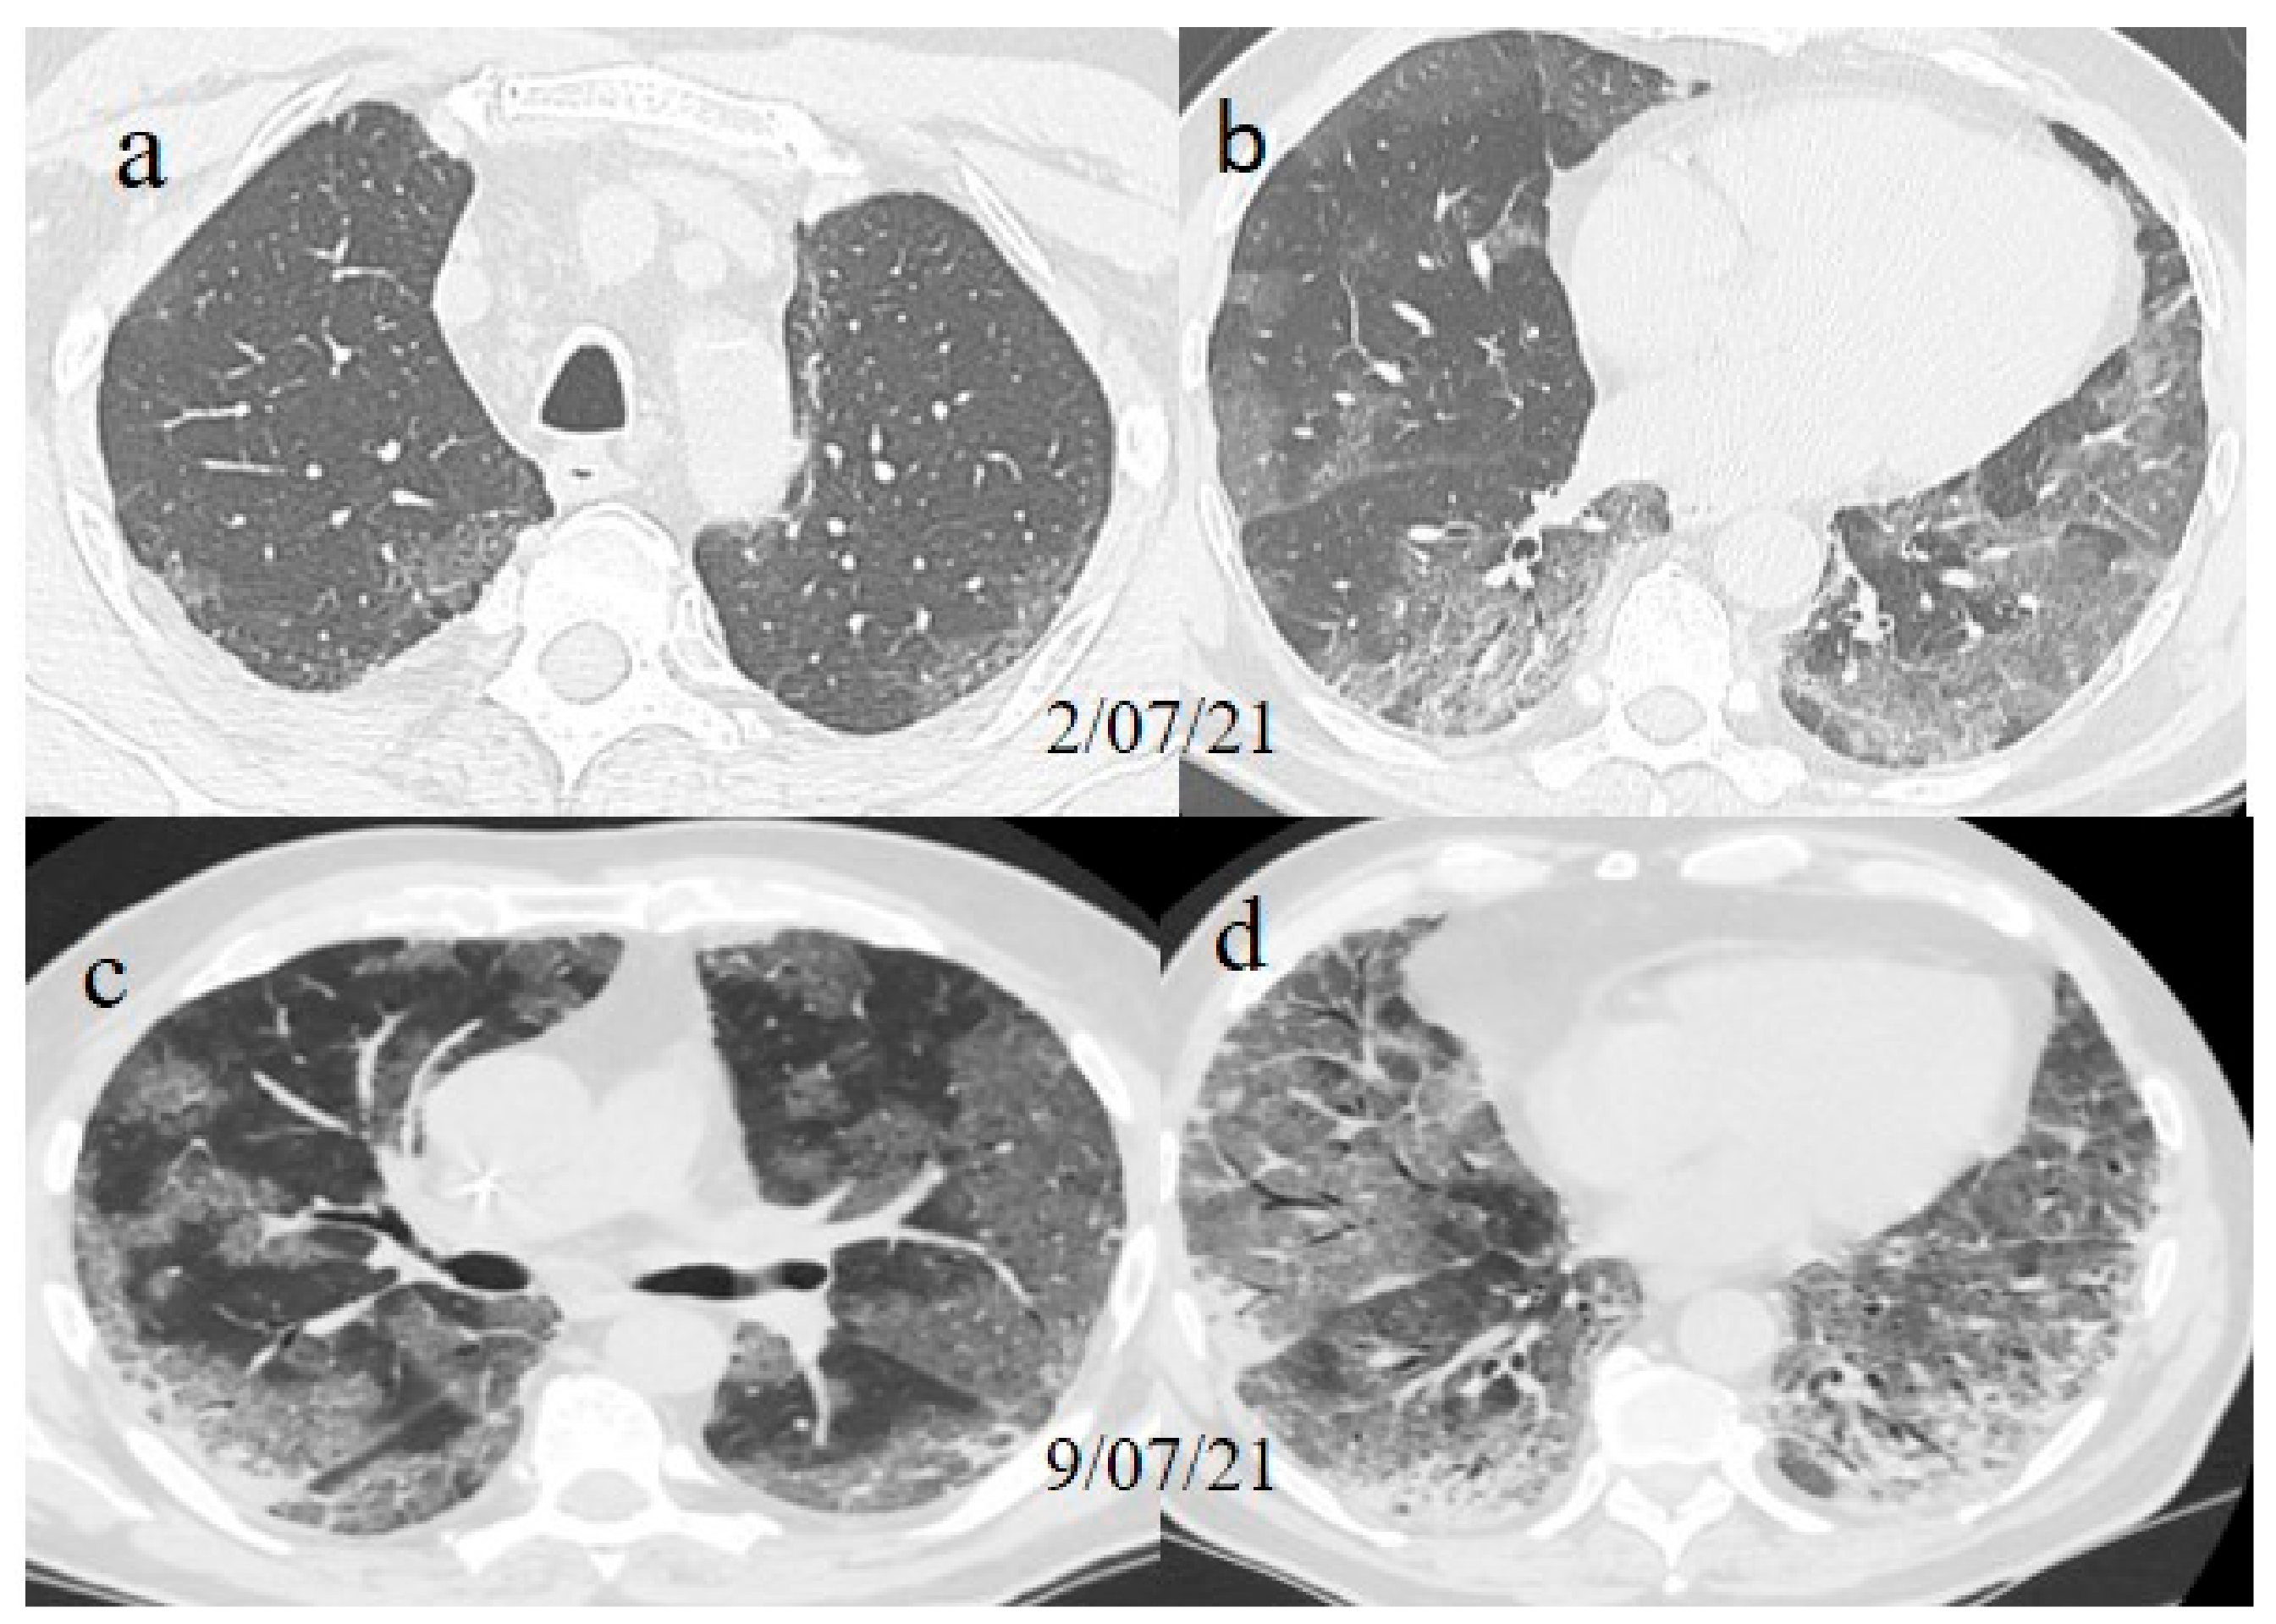

A chest CT showed some small consolidation areas in a peripheral posterior distribution typical of COVID-19 pneumonia, with a CT-SS score of 5/20 (Figure 8).

A 63-year-old woman visited the emergency department of our hospital on 30 July with fever and dyspnea with also thoracic pain. She had a history of previous uterine cancer treated with surgery 10 years before. She had already tested positive for SARS-CoV-2 on 21 July 2021 on an OP/NP swab conducted by an authorized laboratory. She was also fully vaccinated with the COVID-19 mRNA-1273 Pfizer vaccine (first dose on 22 April and second dose on 14 May). She was treated with an oral administration of azithromycin (500 mg 1 cp once daily) for 3 days by her family doctor. However, 2 days before hospital admission, she reported nausea and vomiting. At the time of hospital admission, an NP/OP swab tested positive for SARS-CoV-2, however, without the detection of any variants. The woman reported that her relatives, including her husband and daughter, were also fully vaccinated against COVID-19, and they had also tested positive for SARS-CoV-2. Her daughter reported recent contact with her boyfriend, who had also tested positive for SARS-CoV-2 prior to the daughter’s COVID-19 infection. The daughter’s boyfriend was also fully vaccinated. On hospital admission, during laboratory examination, the woman showed mild elevations in CRP (3.98 mg/dL), LDH (309 IU/L), and the D-dimer (0.51 mg/L). The other laboratory values were within the normal range. Her SO2 level was at 94%. However, due to also to the history of previous uterine cancer and the presence of dyspnea a chest CT was made in an emergency. On the chest CT, some GGO areas were found in a peripheral distribution, suggesting COVID-19 pneumonia with a CT-SS of 5/20 (Figure 9). No serology for SARS-CoV-2 was performed. Treatment with ceftriaxone (1 g once daily with intravenous administration) was started, together with dexamethasone (4 mg once daily with intravenous administration) and LMWE 4000 IU (once daily with a subcutaneous administration). The patient’s clinical conditions improved, and she was discharged after 3 days.

On laboratory examination, the patient showed a mild low level of hemoglobin (Hb, 12 g/dL), a low level of platelet counts (129.000/µL; normal values 150.000–400.000/µL), a mild elevation of D-Dimer levels (1.28 mg/L), and a mild elevation of CRP (3.02 mg/dL). The other laboratory values were within the normal limits. His SO2 level was at 95%. Brain and chest CT scans were performed in the emergency department. No acute lesions were detected on the brain CT, but some GGO with consolidation areas were found on the chest CT on the left inferior lobes with a mild pleural effusion (Figure 10). Treatment with prednisone (25 mg once daily with oral administration for 10 days) was started, together with LMWE 4000 IU (once daily with a subcutaneous administration for 10 days). However, the patient’s OP/NP continued to test positive on 18 and 21 of July, but the patient’s clinical conditions remained stable. Thus, the patient was discharged.

Figure 8. Chest CT performed 13 July showing some small consolidation areas with a peripheral and posterior distribution in the superior lobes (a), part of the superior ad inferior lobes (b) and at the basal level of the inferior lobes (c).

Figure 9. Chest CT performed on 21 July showing some central and peripheral GGO with interstitial thickness and multifocal distribution in the superior lobes (a), in the middle and inferior lobes (b) and in the inferior lobes (c).

Figure 10. Some GGO and consolidation located at the peripheral and posterior inferior lobes, with some consolidation and small pleural effusion (a,b) were incidentally found on the chest CT performed on 7 July for thoracic pain in a patient who tested positive for SARS-CoV-2 and who came to the emergency room for a lipothymic episode.